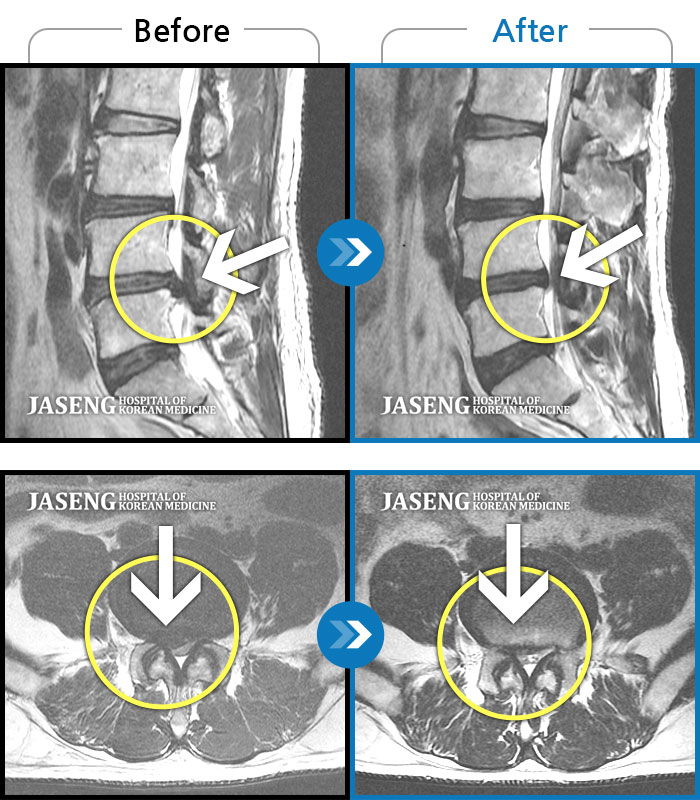

MRI 치료사례

허리 통증과 우측 다리 통증과 저림